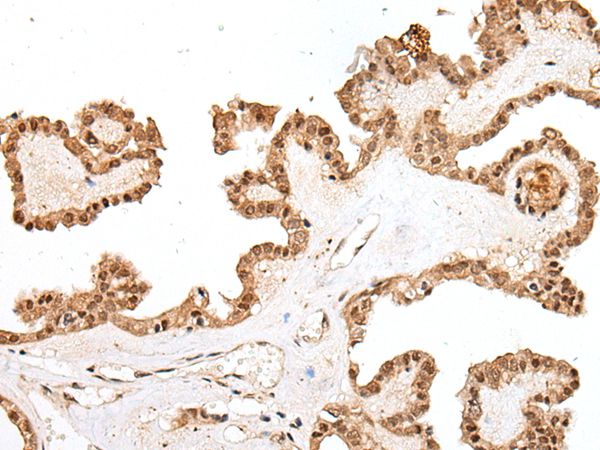

The image on the left is immunohistochemistry of paraffin-embedded Human gastric cancer tissue using PTOV1 Antibody at dilution 1/25, on the right is treated with synthetic peptide. (Original magnification: x200)